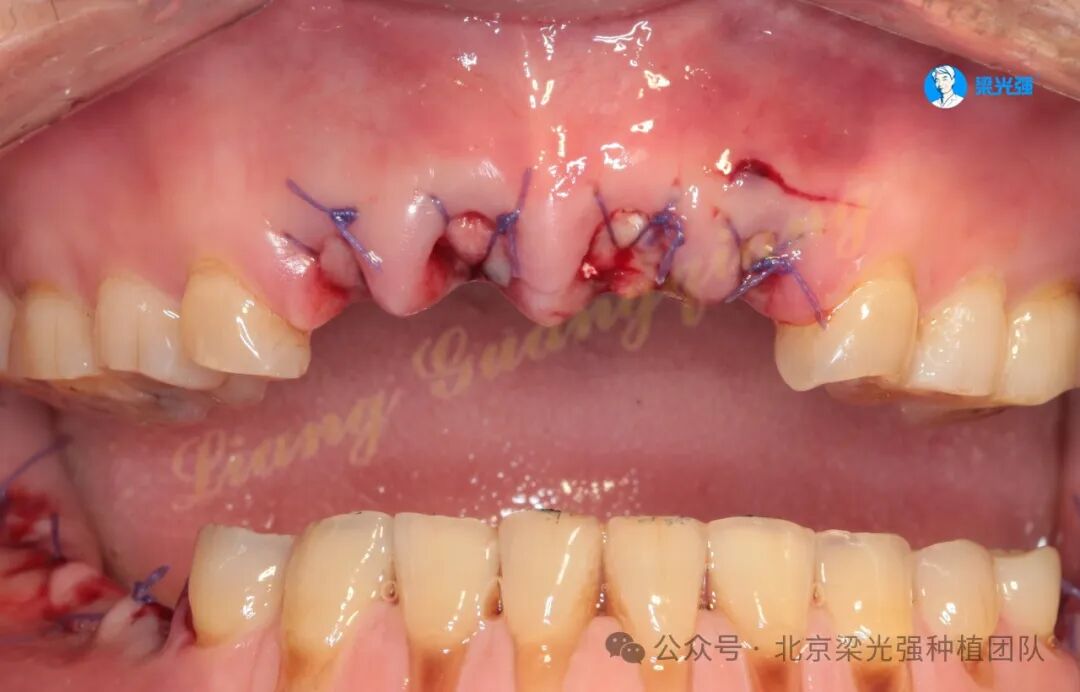

12-22局麻下拔除,先锋钻备洞,用平行杆观测方向,植体植入三要素:位点、方向、深度。首先确定的是位点和方向。

交叉缝合锁住胶原蛋白: